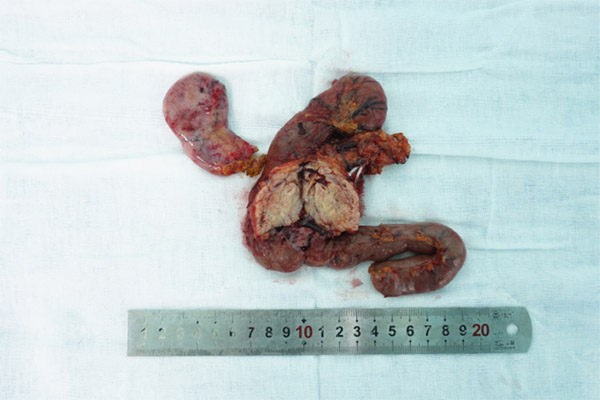

▲术中切除的病变组织

一个月后,陈女士终于完全符合了手术条件。正因为有了精准完善的术前工作,4个小时的手术意料之中地顺利。在3D腹腔镜辅助下,徐进院长凭借高超的技术游离十二指肠、断胰腺、切胆囊,过程中充分保护了门静脉、腹腔干、肠系膜上静脉等重要血管,因此术中出血量不到100毫升。陈女士术后没有出现胰瘘、胆瘘等任何并发症,心脏血流正常,心脏支架功能也没有受到手术的影响。